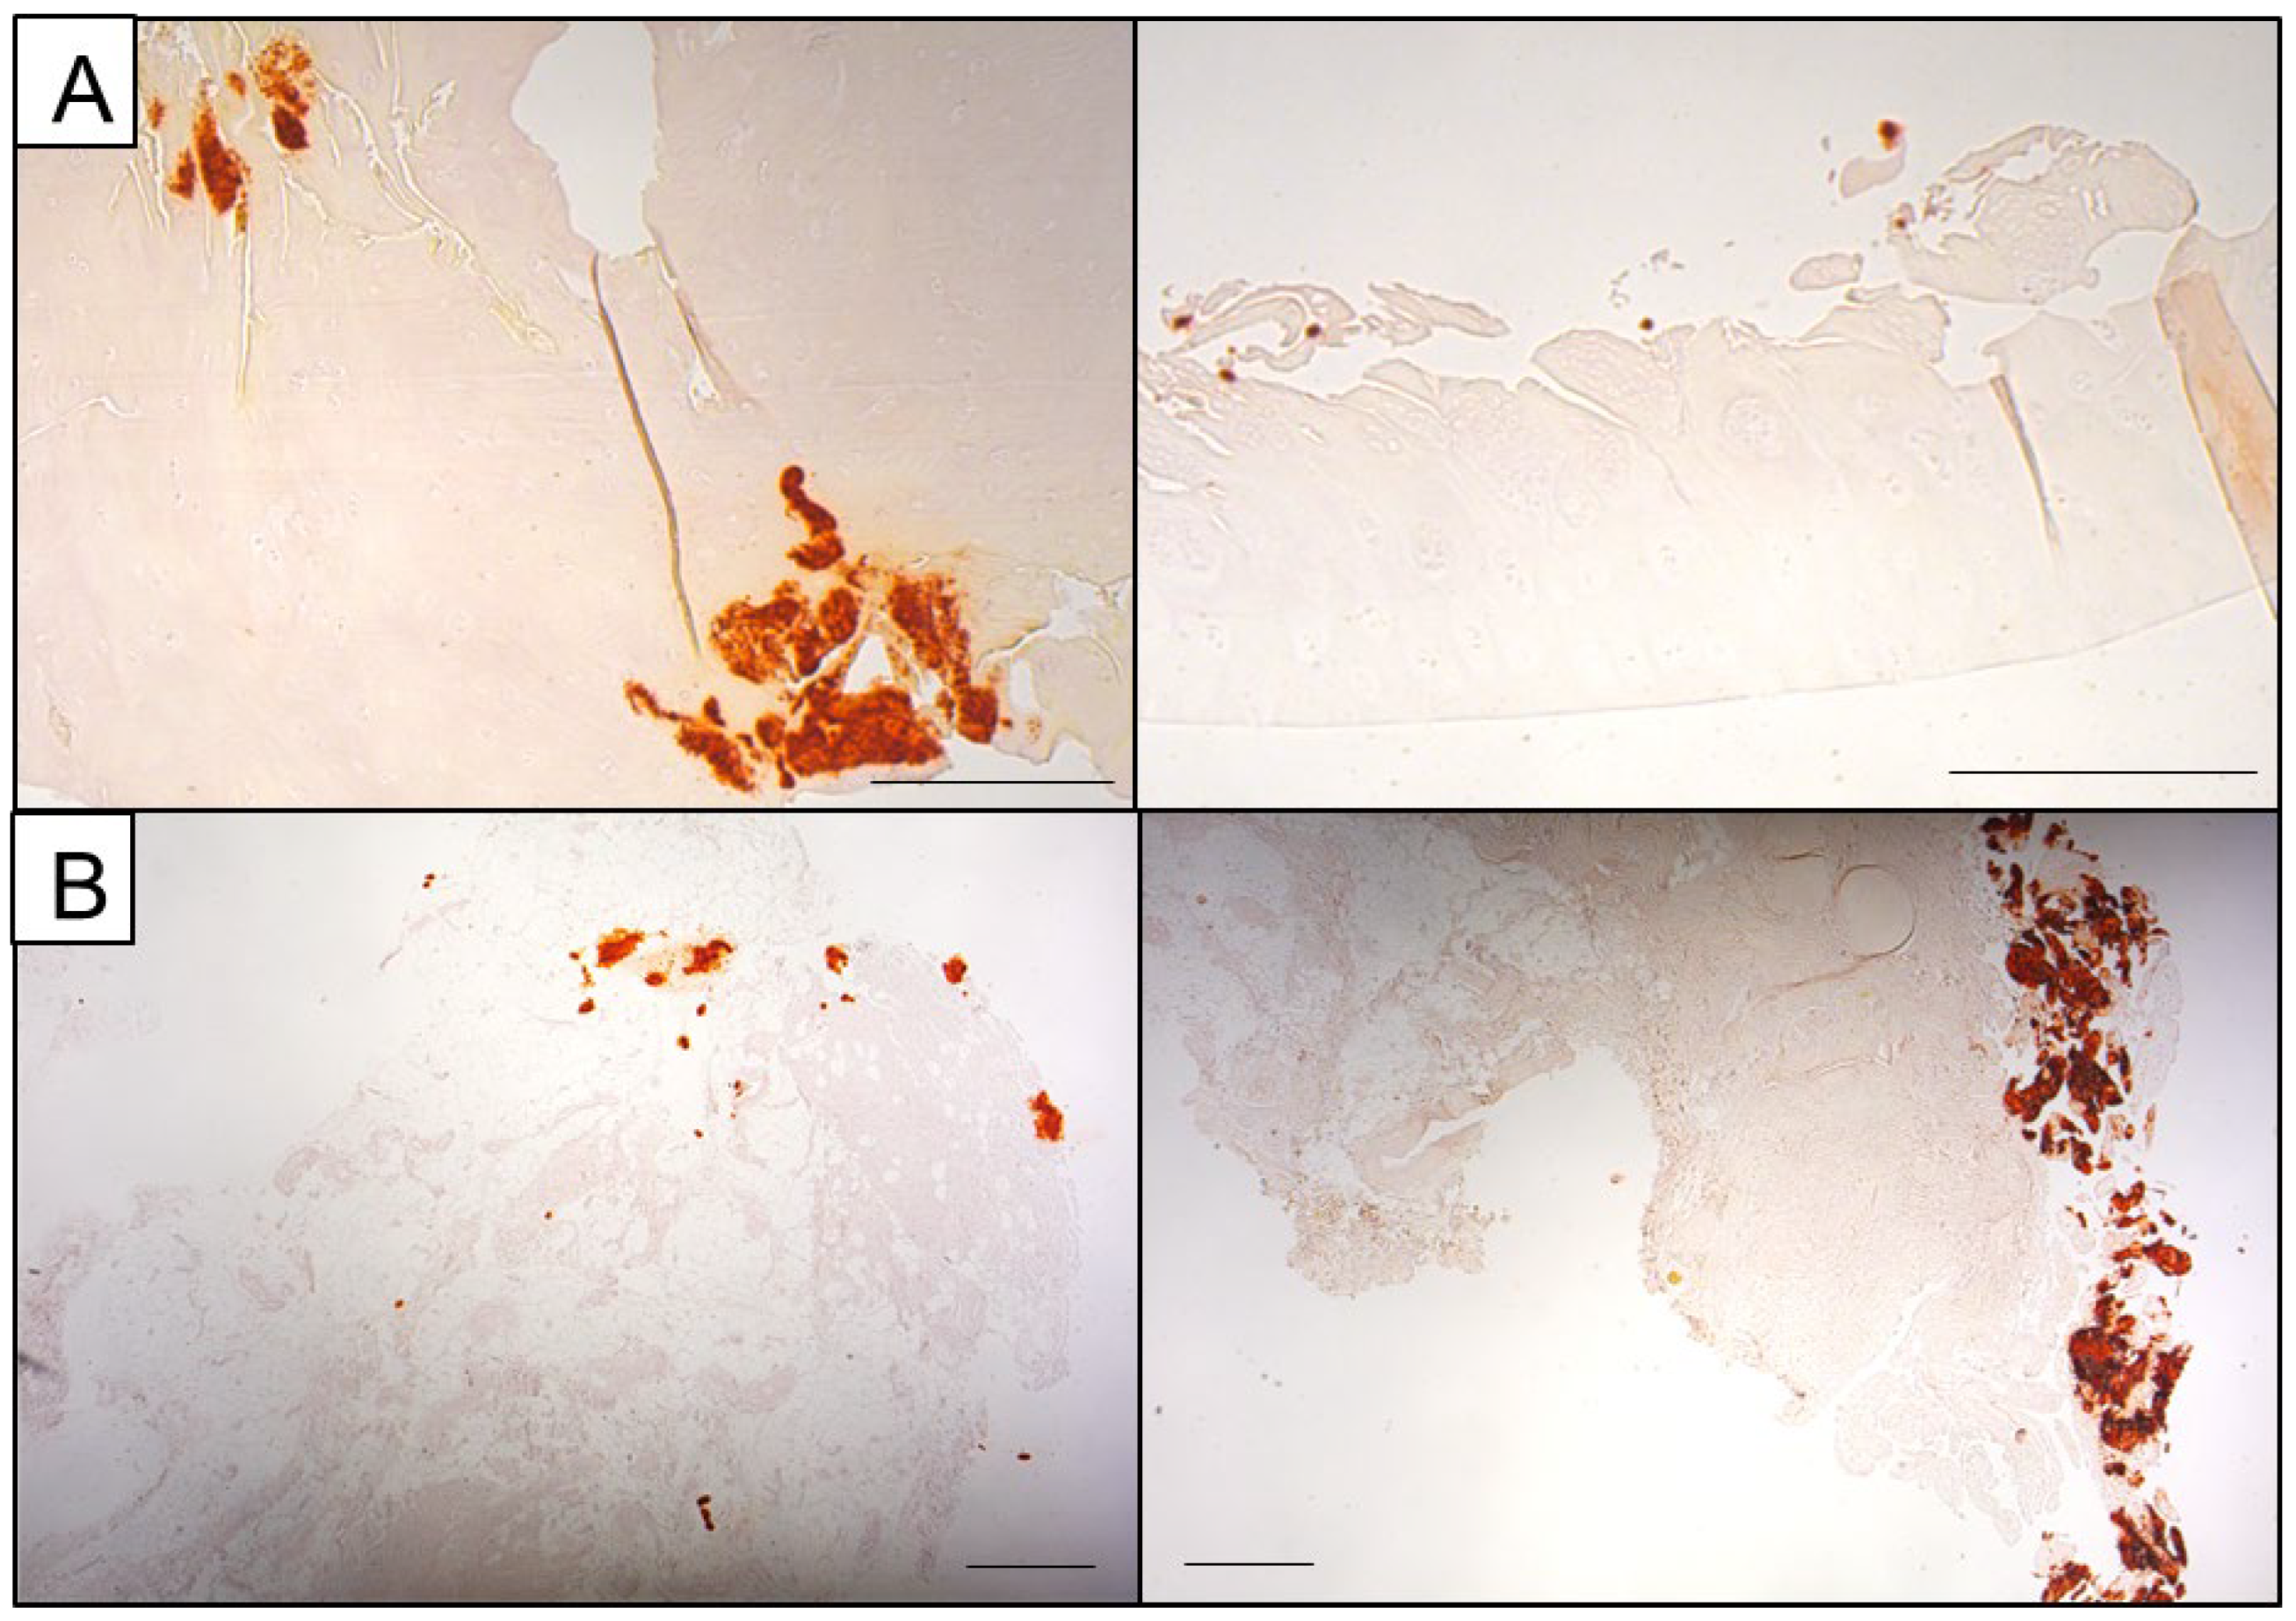

Alizarin Red S stains calcium in a red colour (Figure 1), while Von Kossa marks calcified areas in a black colour, easily visible against the light background (Figure 2). Alizarin red S binds calcium with a high affinity, forming a characteristic red chelation complex. However, the sensitivity of the stain strongly depends on the concentration and pH of the staining solution with overlapping optimal concentration and pH levels for BCP and CPP crystals, impeding accurate differentiation [38].

Figure 1.

Representative images of Alizarin Red S staining of cartilage (A) and synovial membrane tissue. (B) Calcifications appear as dark orange to red deposits within or surrounding the tissue (scale bars: 500 µm).